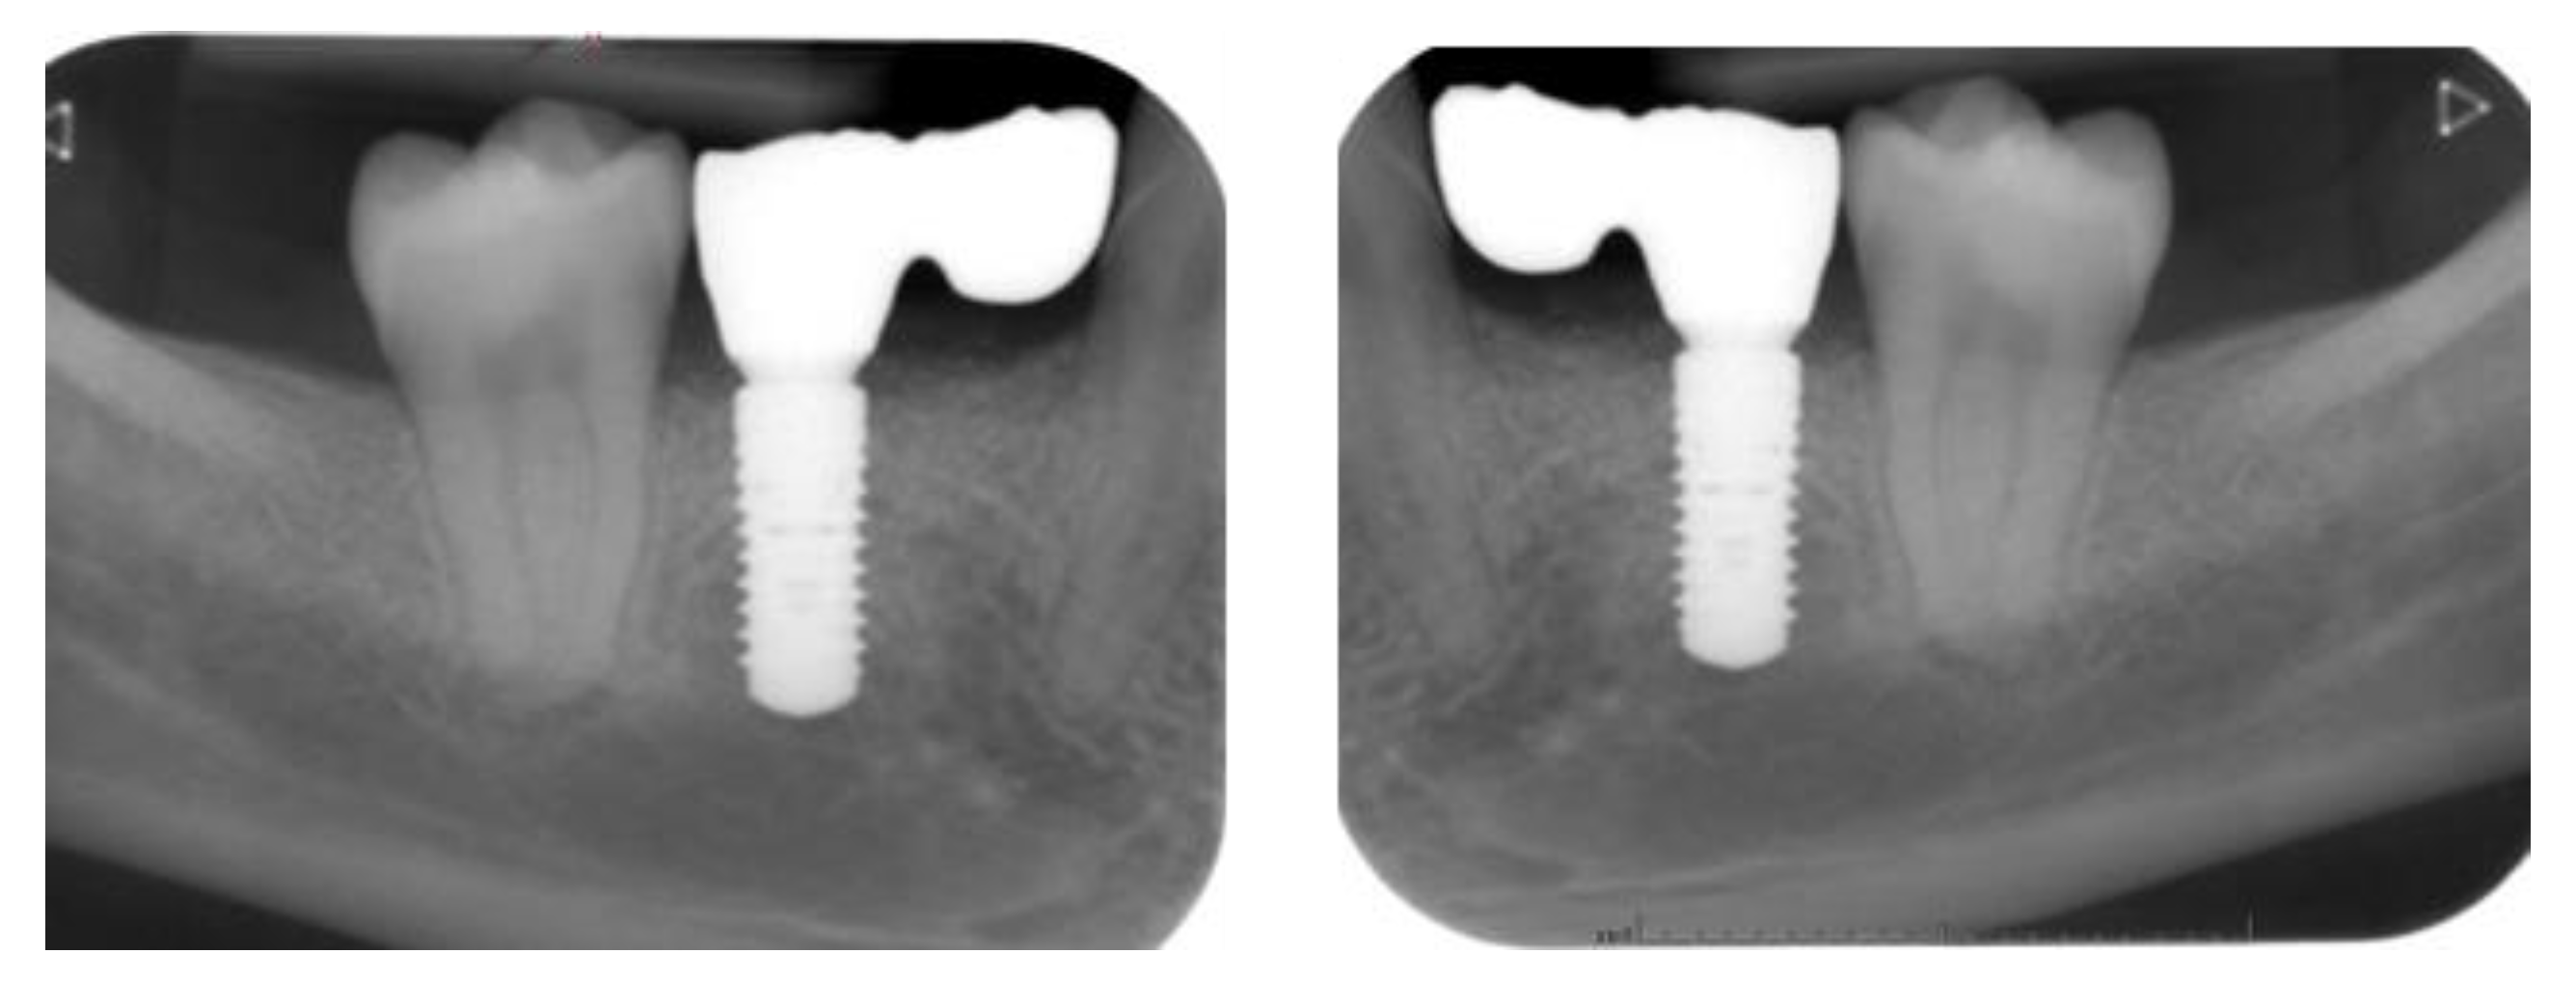

2.5. Individual Cases Description

- Case 1:

- Case 2:

- Case 3:

- Case 4:

- Case 5:

3.1. Clinical Results

3.2. Marginal Bone Level Outcomes